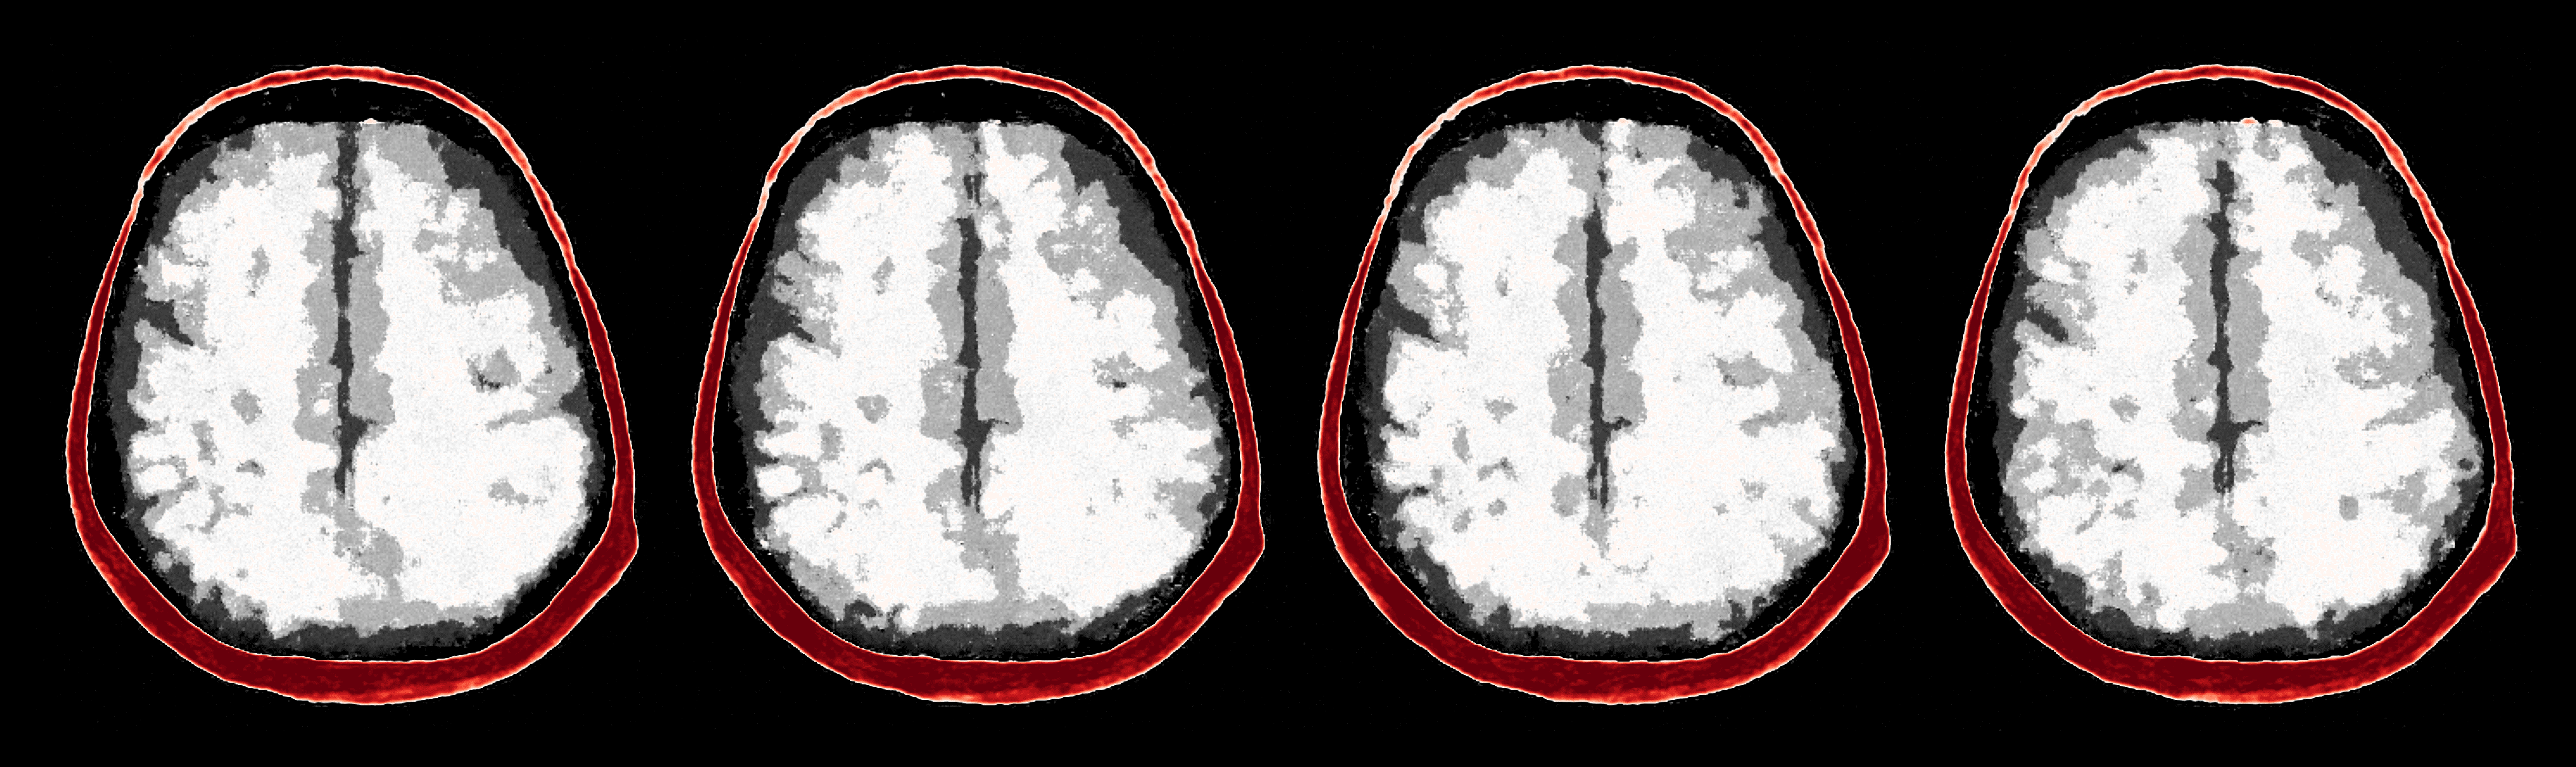

After the refinements of ASPIRE 2, significant improvements are evident in the posterior samples, particularly in capturing the structures within the brain tissue itself. The mean of these posterior samples, displayed in Figure 10, is clearly enhanced in resolution and details. We attribute these enhancements to the increased informativeness of the summary statistic in the second iteration compared to the information yielded by the initial iteration. A detailed inspection of the second summary statistic (shown in Figure 8) reveals more detail on the internal brain structures. Unlike the first summary statistic (cf. Figure 8), which primarily delineated the skull, the second iteration’s summary statistic better ‘illuminates’ the softer tissues within the brain, offering a more informative image for the posterior network. Thanks to accounting for the scattering at the skull, the acoustic illumination of the brain is improved significantly. Accurately resolving the skull structure is an important consideration as noted by [65].

As one can observe from Figure 10, the reconstruction quality improves for increasing number of refinements of ASPIRE. By virtue of the iterative recalculation of the score-based summary statistic, the method is progressively able to discern finer details within the brain albeit the updates become less pronounced as the number of refinements increases. We further illustrate this refinement by plotting posterior samples from all four ASPIRE iterations in Figure 21. Practically, a user of ASPIRE can decide on the number of refinements based on the amount of compute available or by refining until there are diminished returns on enhancements.